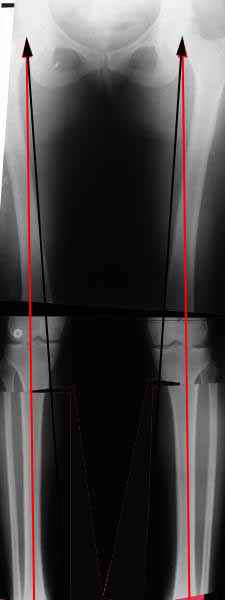

Вот, с учетом и без учета, и на разных уровнях...

Из приведнной схемы не совсеим понял что означают разноцветные линии.

И зачем латерализация периферического фрагмента. Я всегда делаю медиализацию. См схему. И для данного случая медиализация подходит как нельзя лучше.

a> Из приведнной схемы не совсеим понял что означают разноцветные линии.

Черные - это нынешняя механическая ось. Красные - это планируемая правильная ось.

a> И зачем латерализация периферического фрагмента.

;-) Читайте Палея. Стр. 114-115.

a> Я всегда делаю медиализацию. См схему. И для данного случая

Медиализация - это чисто эстетический прием, как я понимаю. Поскольку если делать остеотомию ниже вершины деформации, для восстановления оси надо делать смещение по ширине, в данном случае как раз латерализацию.

А вот на схемке без осей - там на разных уровнях (который правильнее?) устранение варуса чисто открытым клином без медиализации-латерализации. Если как-то так сделать - этого недостаточно будет?